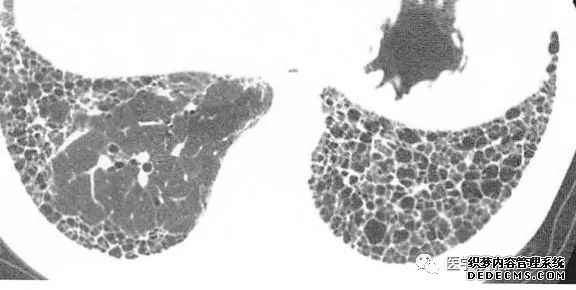

肺转移瘤的十种不典型CT表现